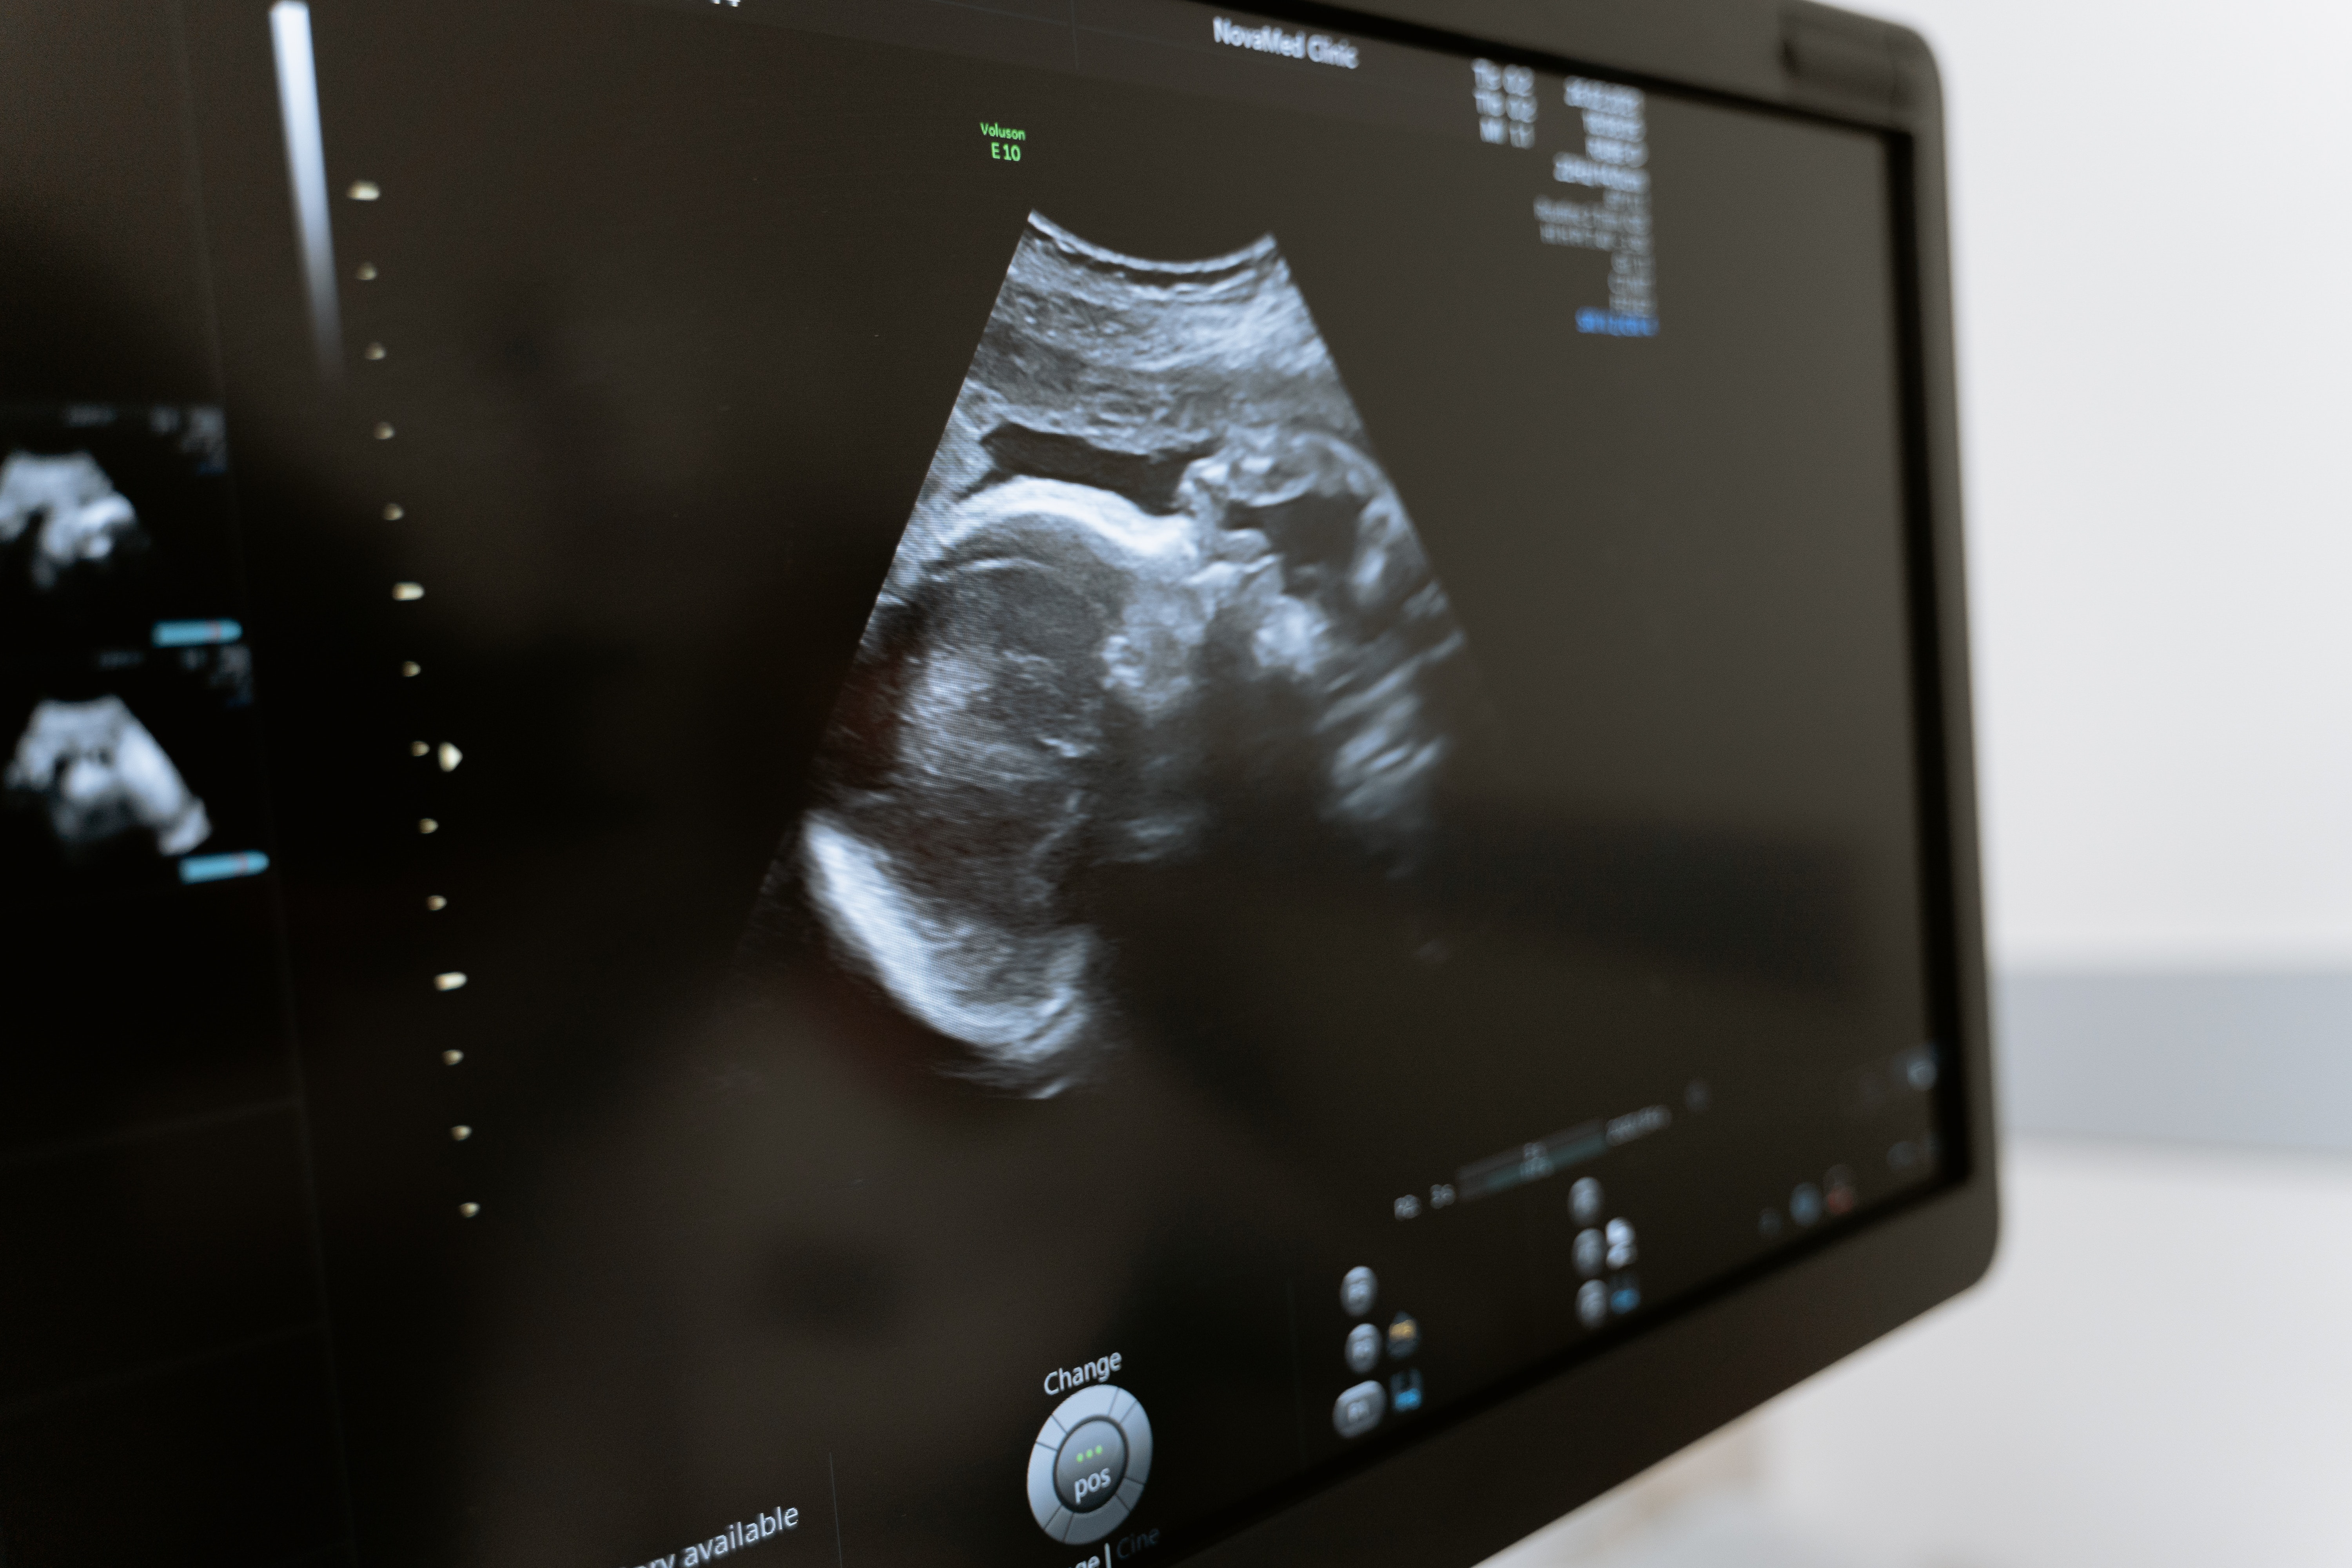

در طول سونوگرافی بارداری، پزشک یا یک تکنسین ماهر از یک مبدل پلاستیکی برای انتقال امواج صوتی با فرکانس بالا از طریق رحم شما استفاده می کند.

سونوگرافی اولیه بارداری به احتمال زیاد به صورت ترانس واژینال انجام می شود، که به پزشکان تصویر واضح تری از کودک شما در این مرحله اولیه می دهد. در این مورد، ارائهدهنده یک پروب مبدل گرز نازک - که امواج صوتی با فرکانس بالا را از طریق رحم شما منتقل میکند - در واژن افراد قرار میدهد. امواج صوتی از جنین در رحم مادر منعکس می شود و سیگنال هایی را به دستگاهی مرکز می فرستد که این انعکاس ها را به تصویری سیاه سفید از کودک شما تبدیل می کند.

اولتراسوند از امواج صوتی با فرکانس بالا برای ایجاد تصاویری از داخل بدن بدون استفاده از تشعشع استفاده می کند. این یک تکنیک ایمن، بدون درد و نسبتا سریع است که حدود 30 دقیقه طول می کشد. تکنسین یک ژل معتدل را روی شکم بیمار اعمال می کند و از یک پروب برای نشان دادن تصاویر اولتراسوند استفاده می کند. سونوگرافی گاهی اوقات به صورت واژینال انجام می شود. اگرچه این روش ناراحت کننده است، اما دردناک تلقی نمی شود. سونوگرافی برای تشخیص بارداری استفاده نمی شود، بلکه برای تعیین تاریخ آن و ارزیابی بسیاری از جنبه های سلامت جنین و مادر استفاده می شود.